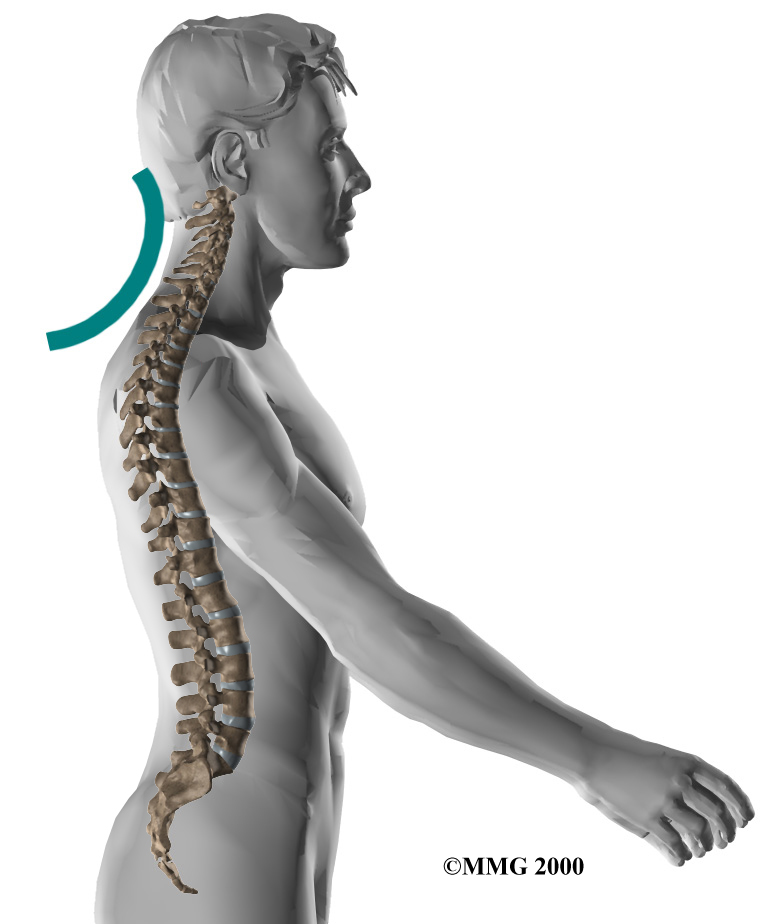

The human spine is made up of 24 spinal bones, called vertebrae. Vertebrae are stacked on top of one another to form the spinal column. The spinal column is the body's main upright support.

Human Spine

The cervical spine is formed by the first seven vertebrae. Doctors often refer to these vertebrae as C1 to C7. The cervical spine starts where the top vertebra (C1) connects to the bottom edge of the skull. The cervical spine curves slightly inward and ends where C7 joins the top of the thoracic spine. This is where the chest begins.

Cervical Spine

Spine Curves